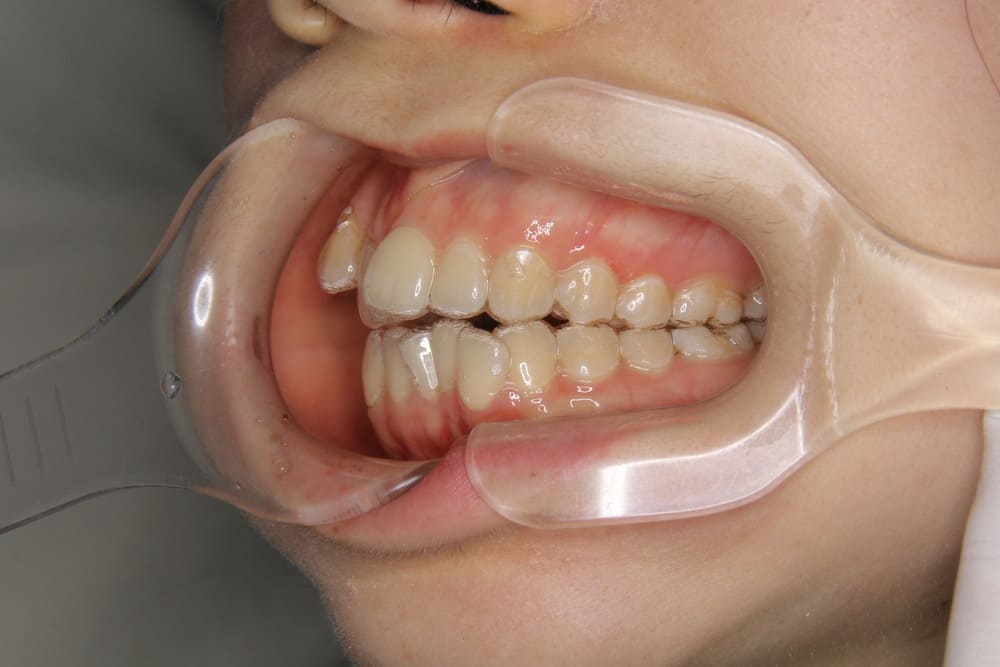

取り外しのできるマウスピース型の矯正歯科治療です。

透明のマウスピースで目立たず、痛みもない矯正装置を使用します。

2精密検査

レントゲン撮影、口腔内写真・顔貌の写真撮影、口腔内スキャナー(iTeroなど)による精密な歯型採得など、治療計画の立案に必要なデータを収集します。